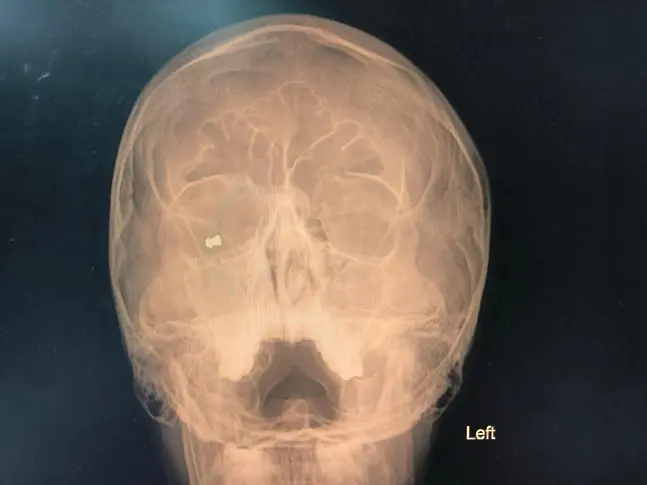

При спешния офталмологичен преглед лекарите установили метално чуждо тяло в орбитата на дясното око, както и разкъсана рана на клепача, съответстваща на входно отвърстие от прострелване.

След пълни изследвания и подготовка, екипът на доц. Яни Здравков извършил спешна хирургична интервенция, при която успешно отстранил металното чуждо тяло - сачма от въздушна (газова) пушка.